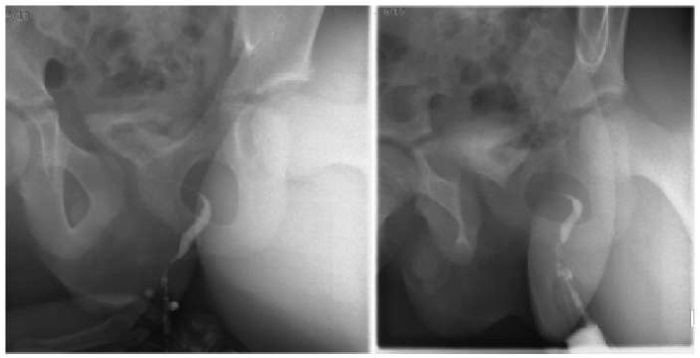

Принято решение о проведении пробы с метиленовым синим: в мочевой пузырь введен контраст, спустя час после введения отмечено капельное выделение контраста через точечное отверстие, расположенное параректально в проекции 3 часов условного циферблата (рис. 5). После подтверждения сообщения мочевого пузыря с параректальной областью был выполнен ряд исследований, направленных на визуализацию выявленного свищевого хода — фистулография (рис. 6) и КТ-3D-моделирование. Фистулография с введением водорастворимого контраста позволила верифицировать расположение и протяженность свищевого хода (протяженность до 6,0 см, наибольшим диаметром в дистальных отделах — до 0,5 см). Также подтверждено сообщение с мочевым пузырем в области шейки, контраст достоверно определялся в полости мочевого пузыря. КТ-3D-моделирование детально определило топографию и синтопию свища (рис. 7).

Рисунок 6.

Фистулография с контрастированием (фото из архива кафедры детской хирургии и урологии — андрологии им. Л.П. Александрова)

Figure 6.

Fistulography with contrast (photo from the archive of the L.P. Alexandrov Department of Pediatric Surgery and Urology–Andrology)

Рисунок 7.

КТ-моделирование свищевого хода (фото из архива кафедры детской хирургии и урологии — андрологии им. Л.П. Александрова)

Figure 7.

CT modeling of the fistula tract (photo from the archive of the L.P. Alexandrov Department of Pediatric Surgery and Urology–Andrology)